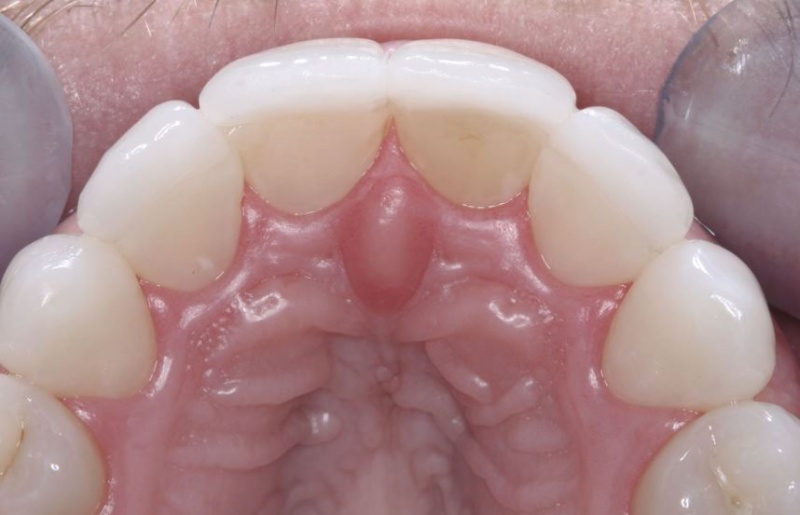

- Tooth Preparations

- Clinical: Soft-Tissue Management and Tooth Preparations